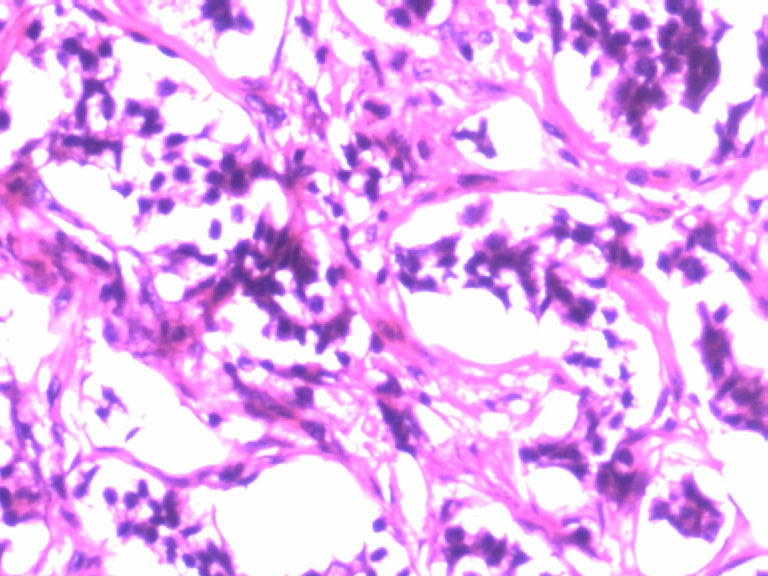

男,50岁,阑尾长7厘米,直径0.4---0.6厘米。剖开:尖端看见淡黄色区,不规则,界限欠清,0.15*0.2厘米,质中。

考虑阑尾类癌